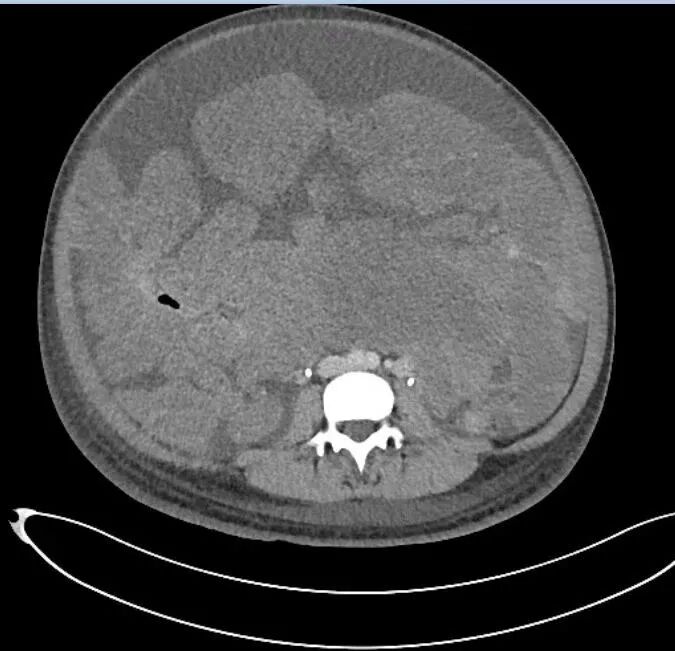

当小曼的CT片子一张一张被贴在阅片灯箱上之后,我沉默了。报告上写道:盆腹腔巨大融合性分叶状包块,下端达盆底,上端达剑突,肠管表面及肠系膜间多发低回声结节,无法计数……

(小曼的腹部CT片,灰度稍高的不规则团块均为肿瘤)